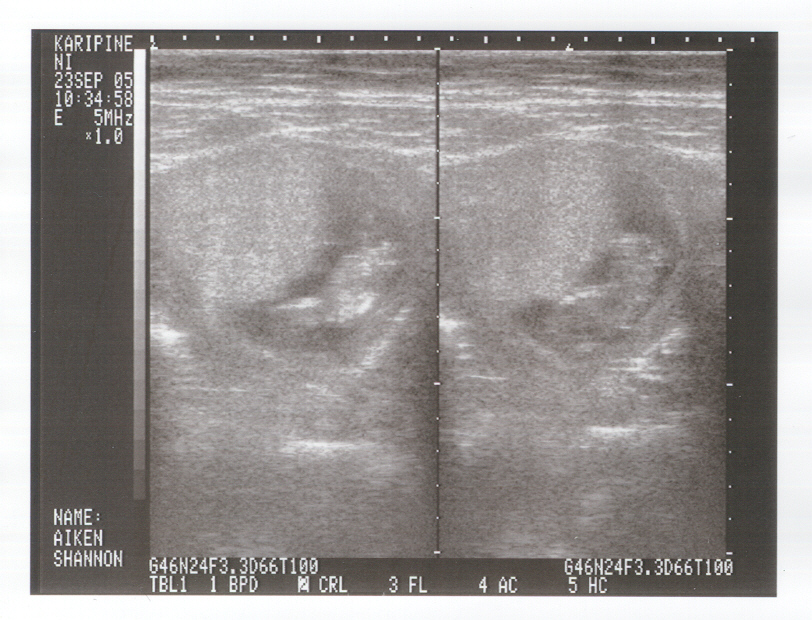

11 Weeks: